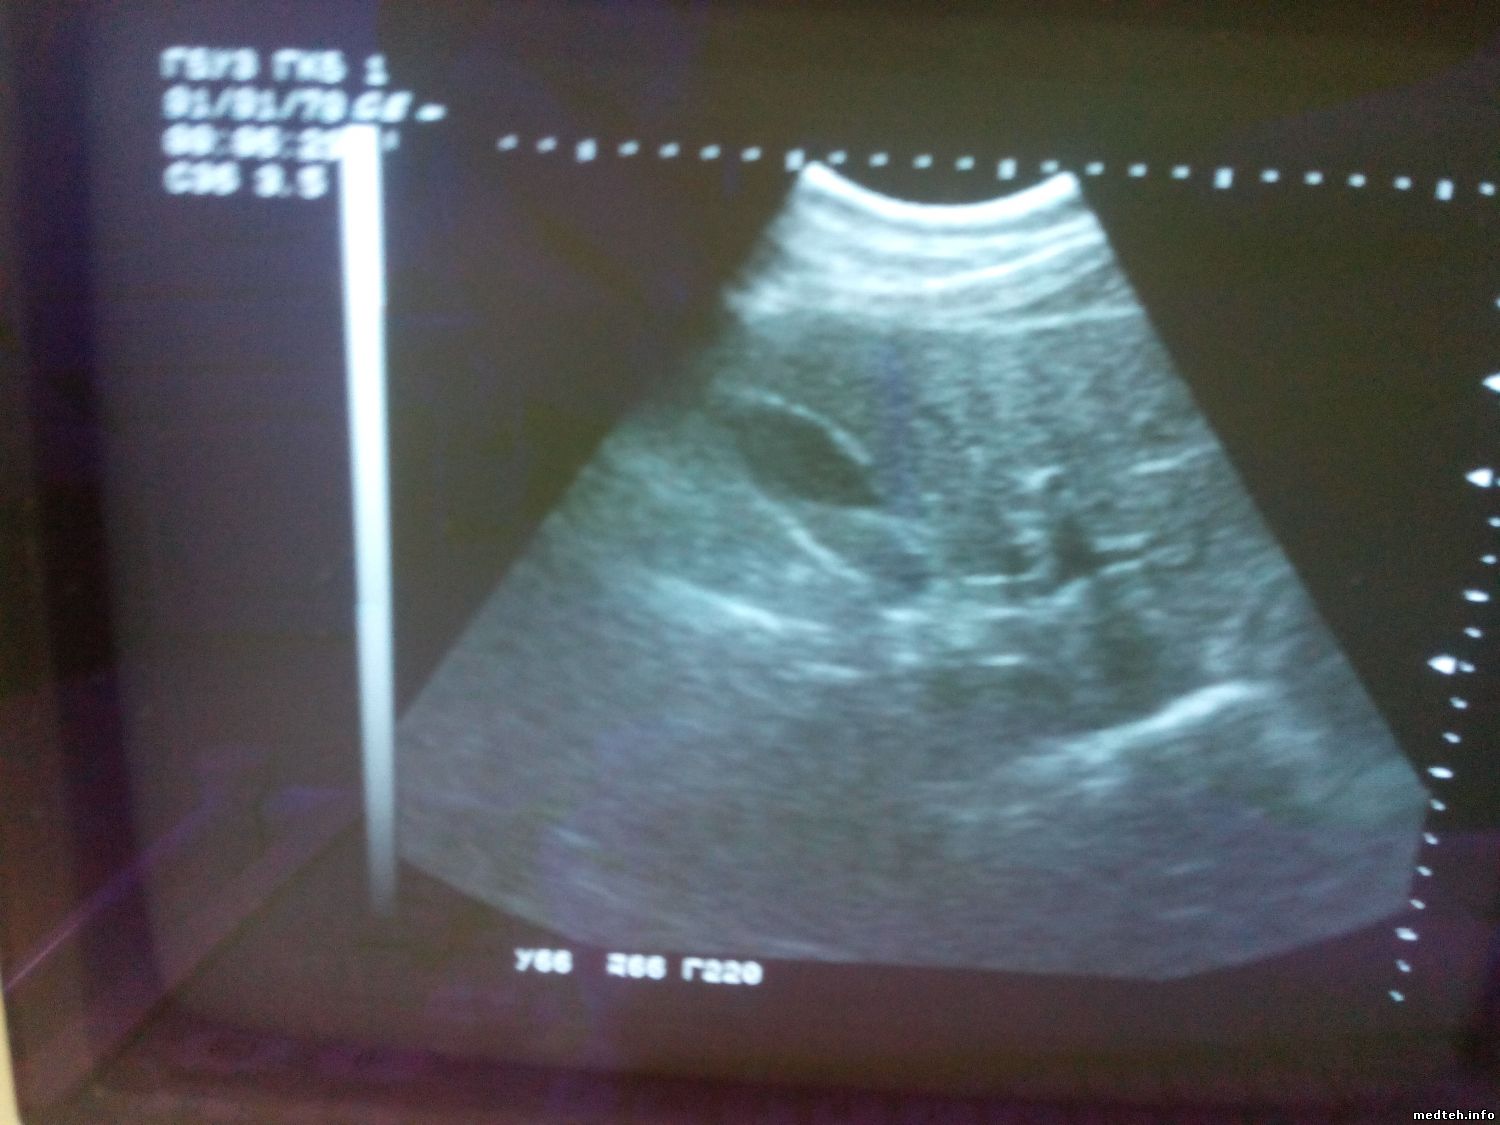

Товарищи помогите разобраться. В УЗИ не спец, просто хотелось бы выяснить характер неисправности.

GE Logic 100 (переносной), датчик конвексный, на фото изображение желчного пузыря, половина черная, половина серая, докторишка говорит, что так не должно быть, должен быть весь черный. Это может быть неисправность датчика? Про линейный мне внятного ничего не сказали, якобы на нем также (хотя другие врачи сказали, что его не используют вообще). На конвексном датчике с виду линза в норме, выпуклостей и пустот нет, порезов тоже нет.

7966679.jpg (112.4 Kb)